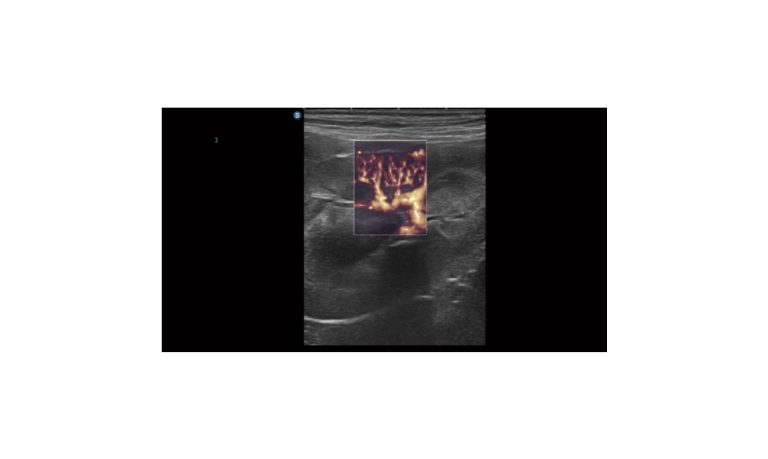

SonoScape Pro Pet E11

Smart Imaging

Introducing the first portable ultrasound with the C-Field+TM platform, redefining diagnostic imaging. Designed for veterinarians, it delivers unmatched clarity, ultra-fast processing, and seamless adaptability for all species. Experience Smart Imaging, Heartfelt Care—anywhere.

Equipped with cutting-edge veterinary software and optimized workflows, it embodies our commitment to Smart Imaging, Heartfelt Care – Wherever Their Journey Leads, with unparalleled performance and adaptability, this innovative system empowers veterinarians to provide exceptional care across all diagnostic applications,